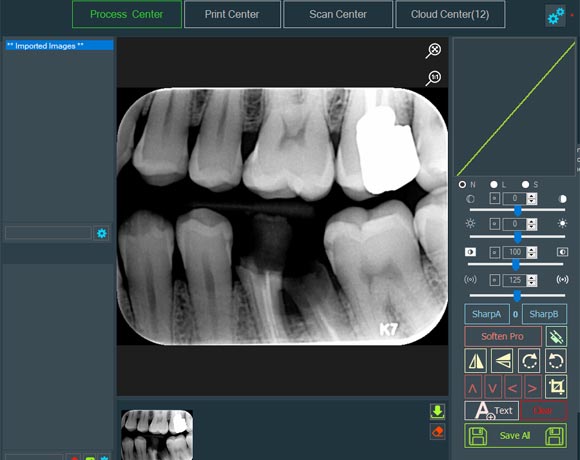

سیستم جامع انتقال عکس پزشکی

نسخه ، انتقال و آرشیو دیجیتال

نرم افزار جامع رادیولوژی دهان

اسکن ، پردازش و پرینت دایکام